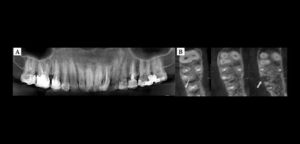

Paciente de sexo femenino y de 59 años de edad es referida al Instituto de Diagnóstico Maxilofacial para realizar el estudio de evaluación ósea para la colocación de implantes, lo cual llamo nuestra atención la presencia de un hallazgo radiográfico en el maxilar inferior.